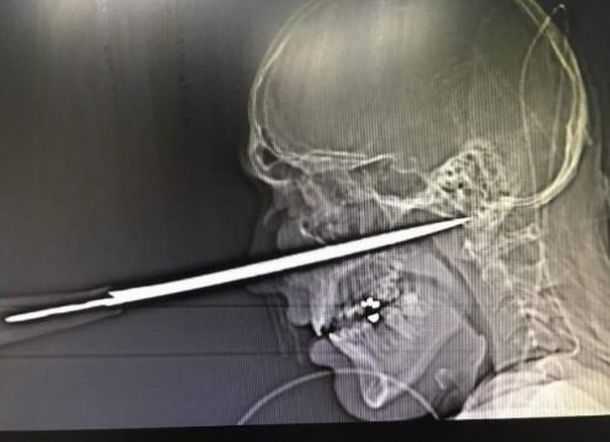

Gambar sinar-X yang mengejutkan menunjukkan ujung pisau yang menempel pada arteri utama di dasar tengkorak pria bernama Robbie Pattinson itu, dikutip dari Mirror Online, Sabtu (15/2/2020).

Mempersiapkan pertarungan pertamanya, Robbie berkata: "Ketika saya melihat gambar X-ray saya menyadari betapa beruntungnya saya masih hidup."